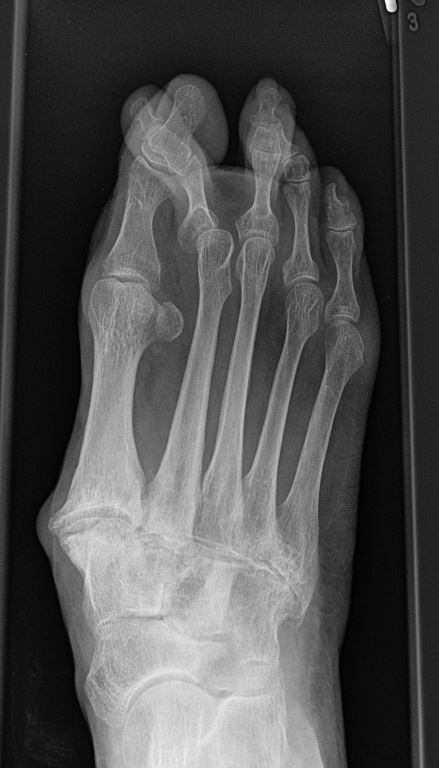

Die Überbelastung im Schaftbereich wird selten von den Patienten wahrgenommen. Manchmal findet sich vor allem am Os metatarsale II proximal eine Stressfraktur. Adaptiert sich der Knochen, kann im Röntgenbild häufig eine Kortikalisverdickung im Bereich der Metatarsale II und III Schäfte als Ausdruck einer vermehrten Lasteinleitung beobachtet werden (Abb. 4).

Zum Lesen der Bildbeschreibung und zur Vollansicht bitte das Bild anklicken. Bild: C. Hase.